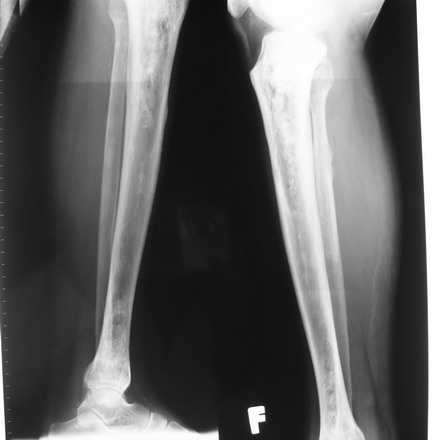

Vào viện ngày 01-11-2007- Chụp X-Quang thường quy: tổn thương hình khuyết xương thành ổ, xơ hóa ở các xương dài hai bên. TD viêm tủy xương chưa loại trừ ung thư di căn xương.

Hình ảnh XQ thông thường của tổn

thương xương chày